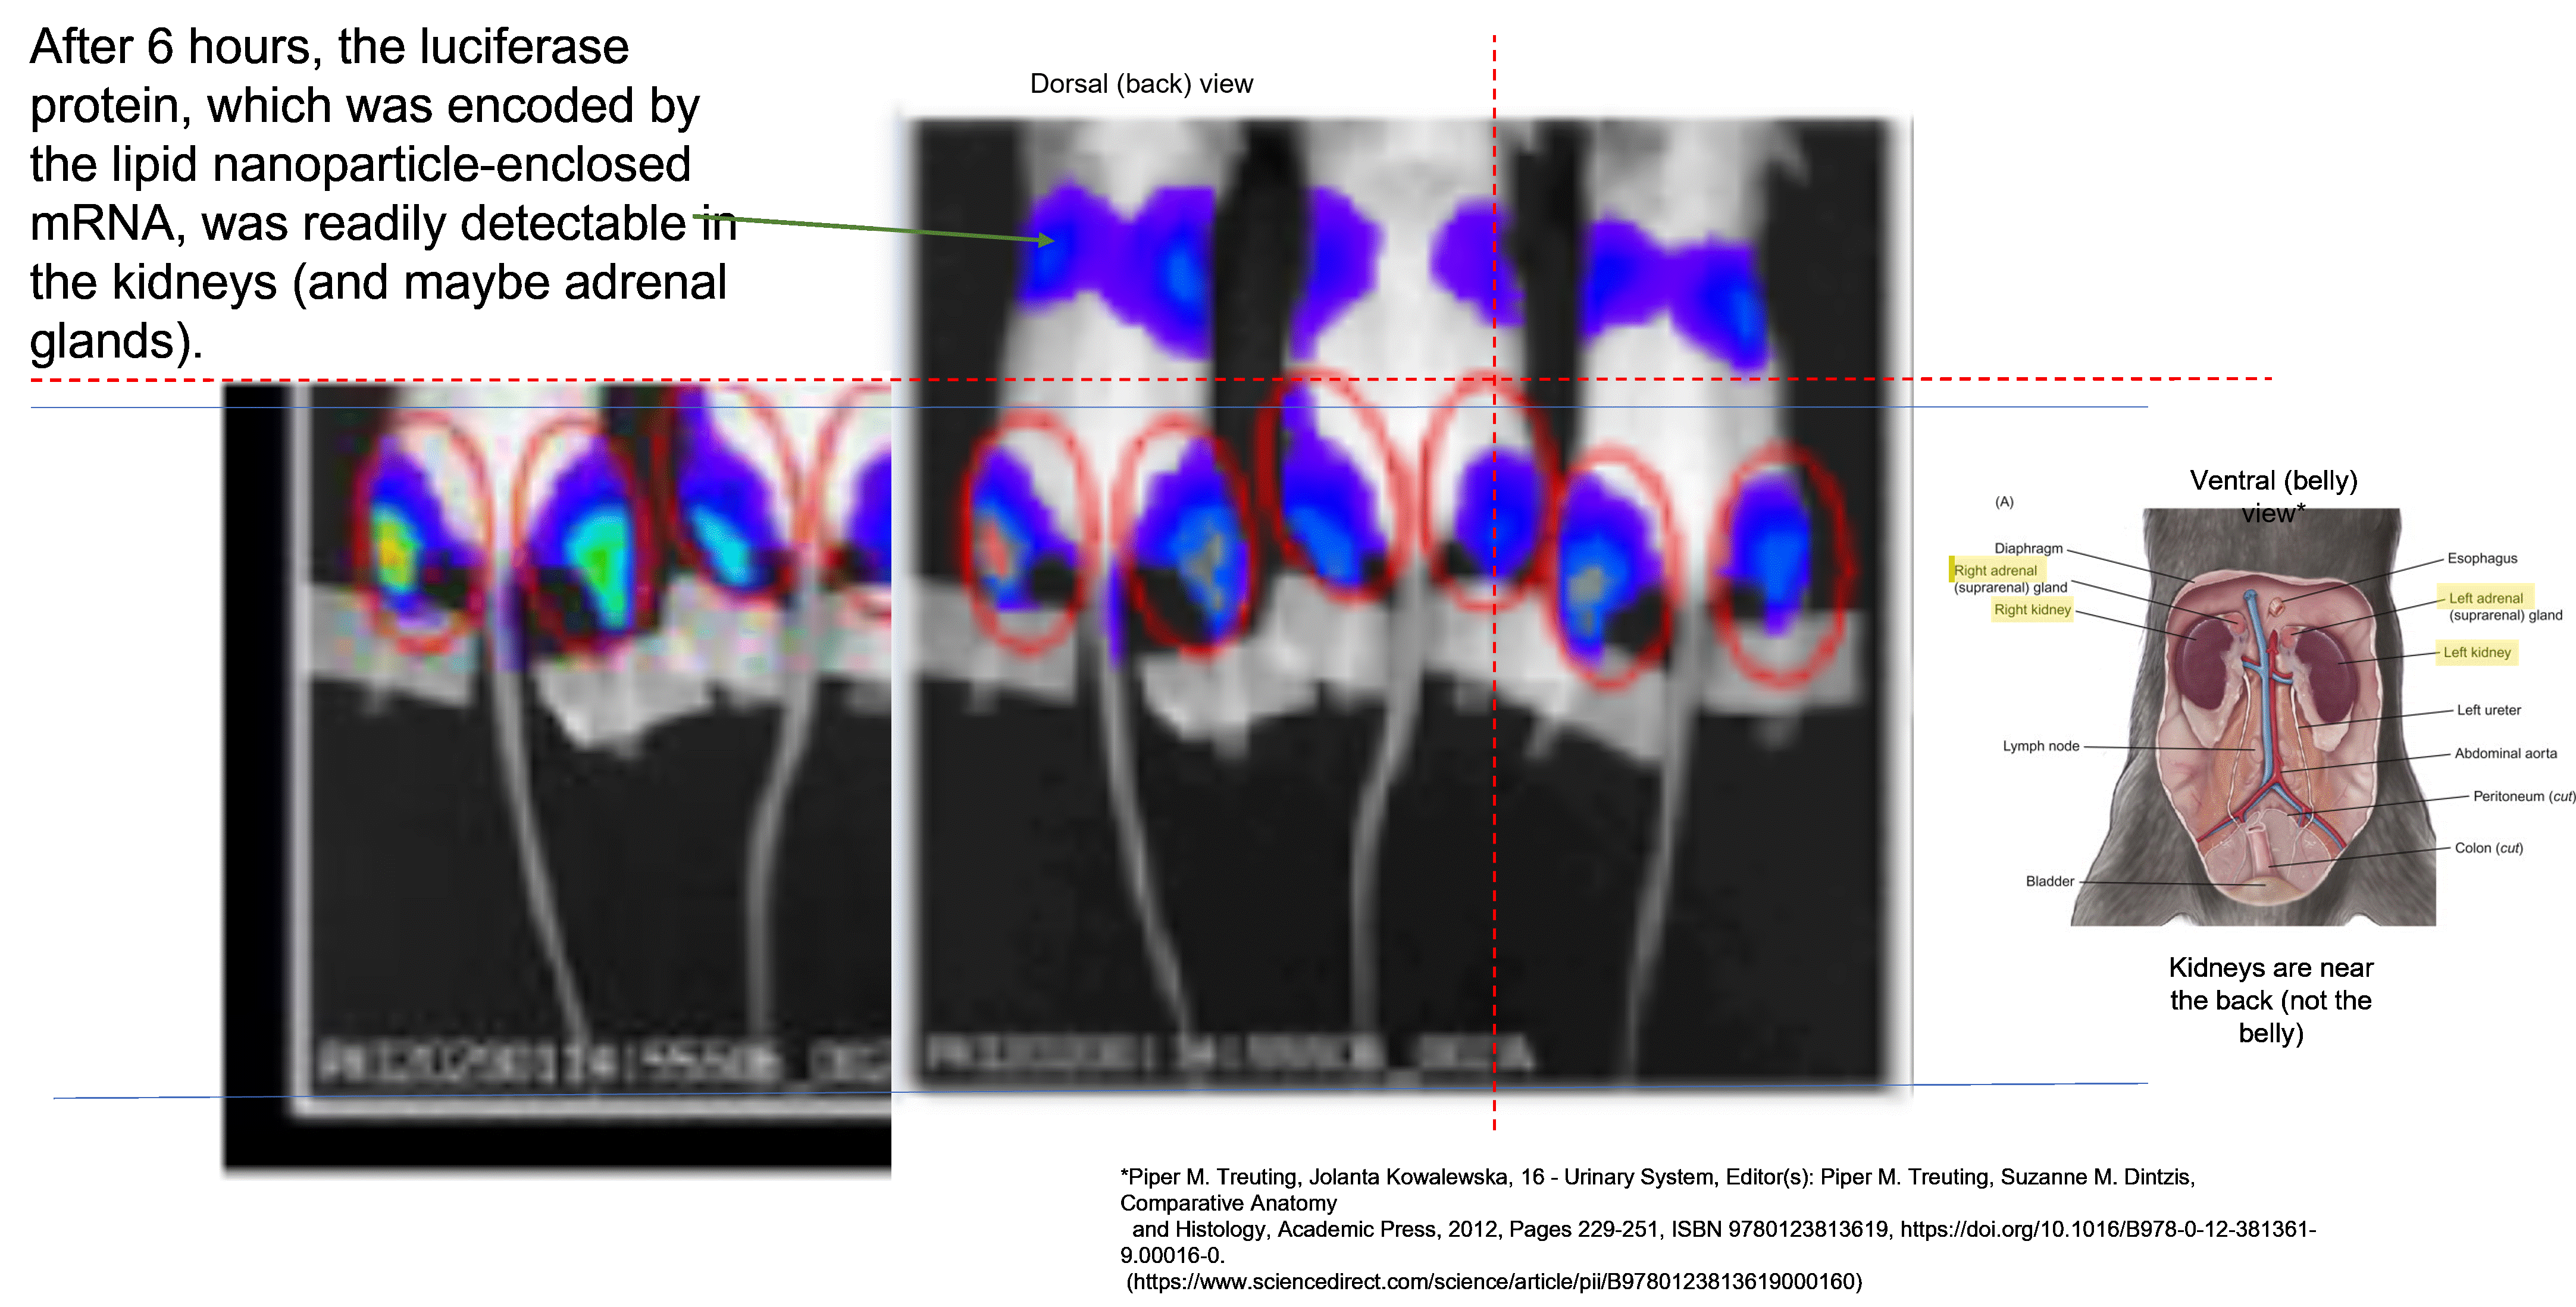

Note the single picture in the bottom left-hand corner. This shows the luciferase signal in two of three mice that had been injected. The ‘vaccine’ was injected into the calf muscle (the one at the back of your lower leg). It is standard practice to do intramuscular injections into the larger muscles of both hind limbs of mice. In people we usually do intramuscular injections into a single shoulder muscle. The problem here is that the leaked version of the earlier report had this figure…

I noticed that the image at the top of the right column of images (the luciferase group at six hours post-injection) appeared to be almost identical to the only image in the official report, but it was not cropped as much. This is very important because the only anatomical location that the ‘vaccine’ reportedly went to outside of the injection site was the liver. So, let’s do a head-to-head comparison between the two images…

It looks to me like the images are identical, but with the signal dialed down a bit in the version on the left (which was from the official report). These mice are on their bellies, so the imaging is of their backs. I can tell you from years of experience working with mice that this pattern is suggestive of readily detectable expression of the mRNA-encoded protein in the kidneys, with possible involvement of the adrenal glands. This would be consistent with the rat biodistribution study that I previously commented on.

Why were the images cropped to exclude evidence of biodistribution to the kidneys/adrenal glands ?!?